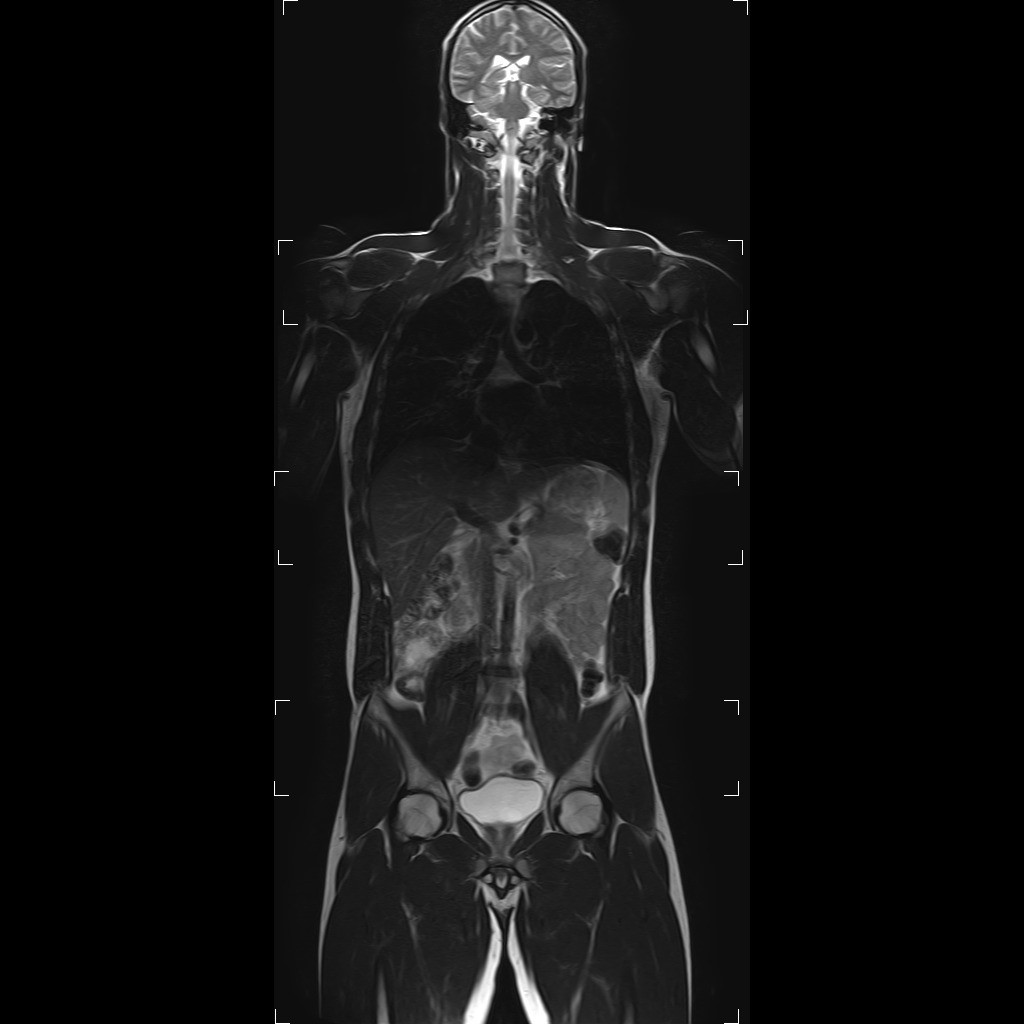

- Preventivní onkologický screening je zaměřen na odhalení bezpříznakového onemocnění, je složen ze specifických laboratorních odběrů, celotělového scanu magnetickou rezonancí a doplňujících vyšetření oddělení zobrazovacích metod. Vyšetření magnetickou rezonancí je vysoce moderní, neinvazivní celotělové vyšetření bez dávky záření, obsáhne oblast od hlavy do poloviny stehen. Laboratorní odběry zahrnují zejm. onkomarkery: celostní, prostatické, střevní a gynekologické (vaječníky + prsa). Odebírá se i FOB (okultní krvácení).